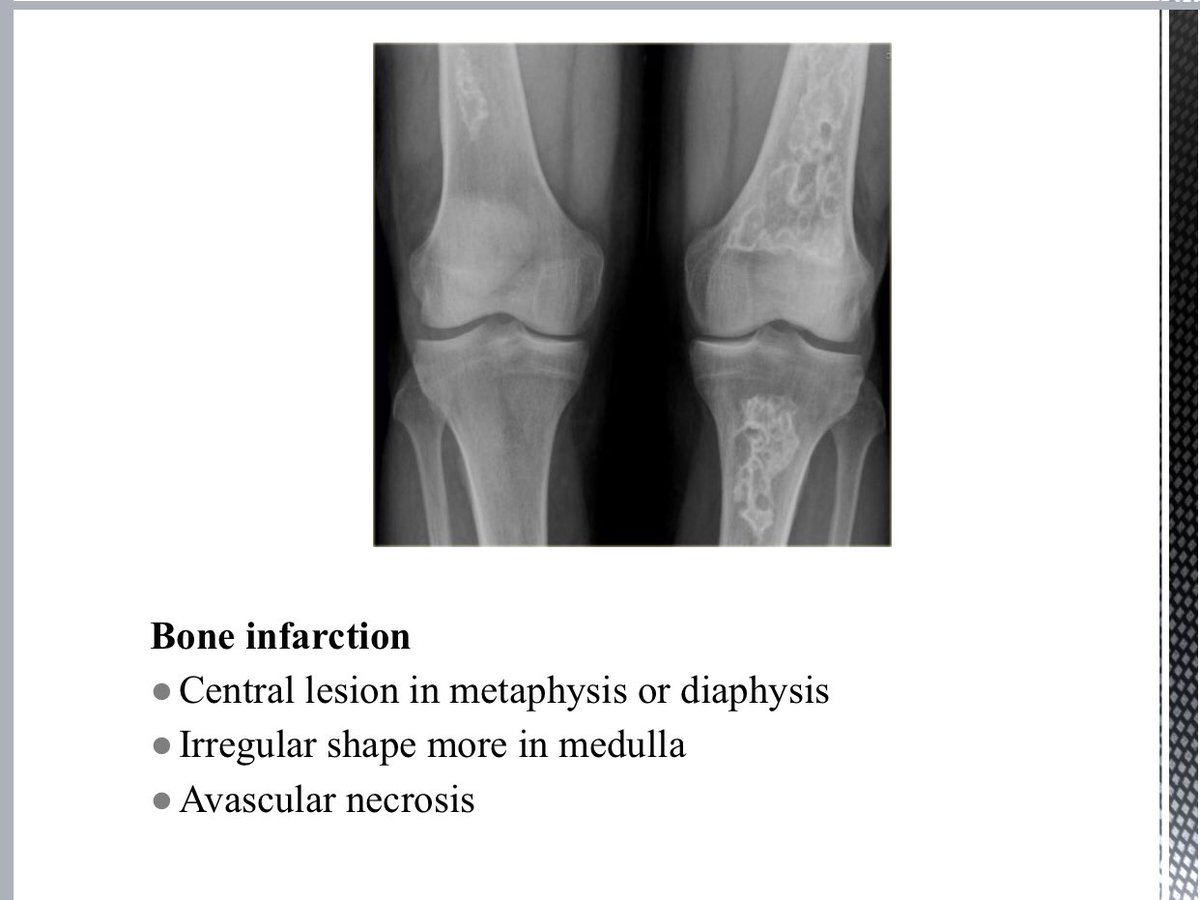

ثريد اليوم مليء بالمعرفة ومهم جداً لـ Skeletal System وأبرز الامراض مع شرحها بشكل مختصر بالصورة والمرض وأبرز العلامات الي من خلالها نحدد نوع Diagnosis راح تفيدكم بشكل كبير سواءً للطلاب أو الموظفين أو الأطباء .